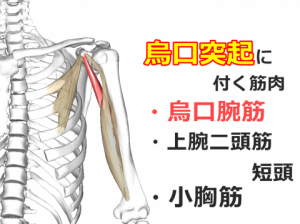

実はこの小胸筋という筋肉は体の前側にあるのですが、肩甲骨の上の方「烏口突起(うこうとっき)」という場所についていて、筋肉が縮こまると肩甲骨を前側に傾かせてしまいます。